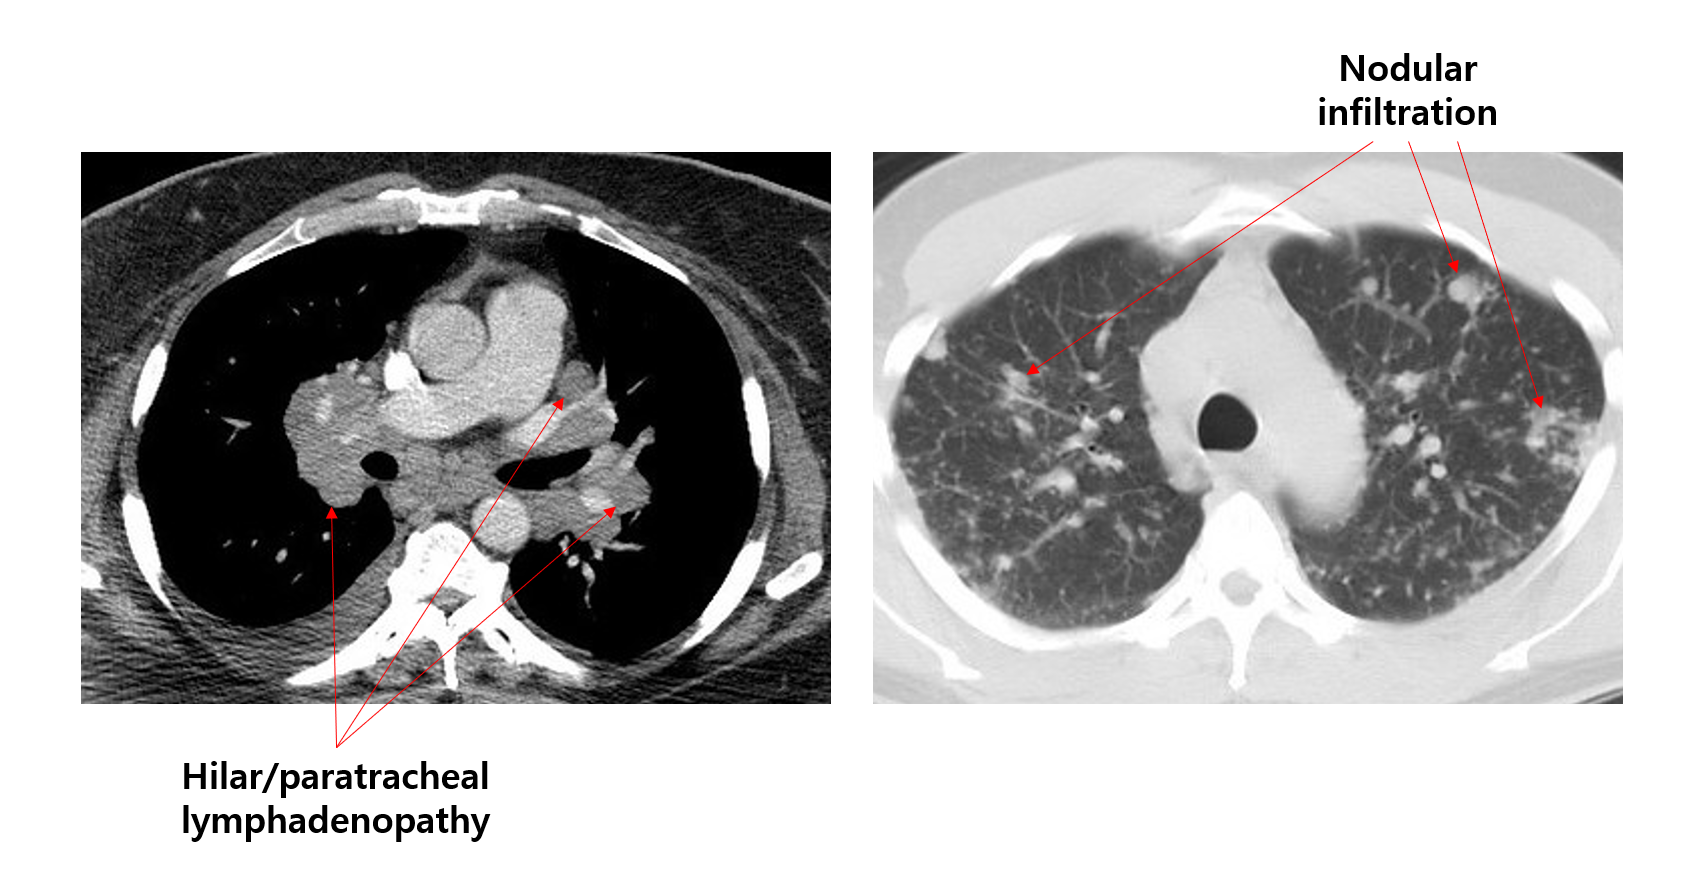

폐문부/기관주위 림프절비대(hilar/paratracheal lymphadenopathy)

② 진행시 다수의 nodule 및 reticular opacity, fibrosis (주로 폐 상부 침범)

(1) CT: LN 비대, nodule, fibrosis 등 관찰 + 타 질환 배제